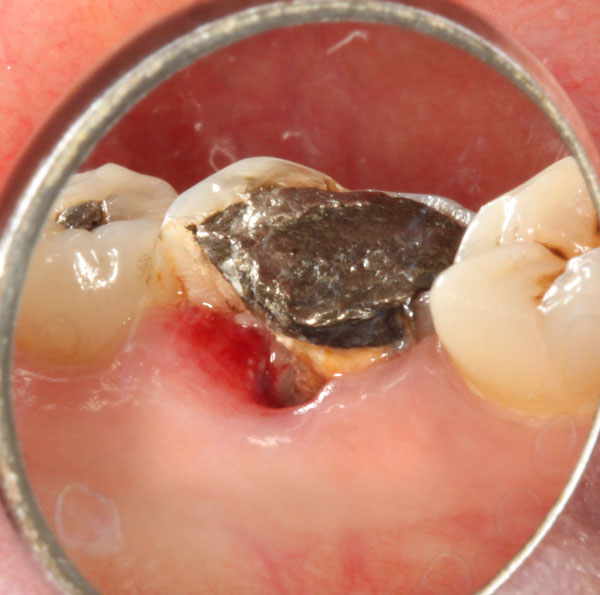

Die Patientin stellte sich als Neuzugang vor mit einer abgebrochenen Zahnwand zungenwärts an Zahn 36.

Foto mit Sicht auf die linguale Seite – fehlende Wand: